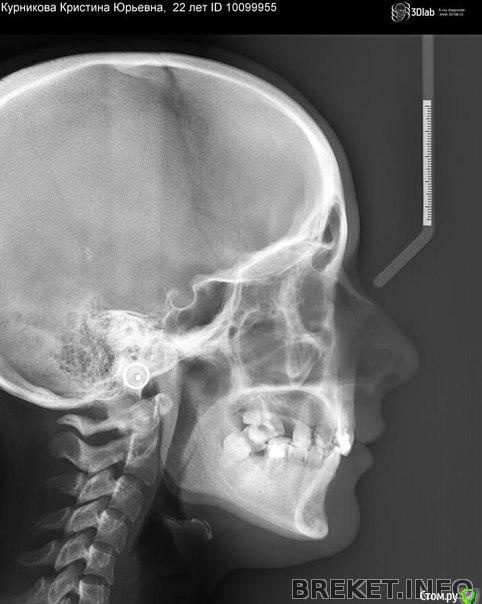

Кристина93 Опубликовано 7 апреля, 2016 Поделиться Опубликовано 7 апреля, 2016 (изменено) Добрый вечер всем. Очень сильно комплексую по поводу нижней трети лица. Прикус 2 класс 2 подкласс, сейчас ношу брекеты, орт говорит что без операции(остеотомии) профиль улучшиться Немного...а меня терзают сомнения что так все и останется...это выступающая вперед верхняя губа...и в целом некрасивое положение губ. Скажите, пожалуйста, стоит ли в моем случае делать операцию по выдвижению нижней челюсти? Я сама только ЗА. Но орт говорит что из-за 2-3 мм не стоит ее делать... Я хочу все сделать чтобы добиться красивого профиля. Помогите , пожалуйста , разобраться Изменено 7 апреля, 2016 пользователем Кристина93 Ссылка на комментарий

Кристина93 Опубликовано 9 апреля, 2016 Автор Поделиться Опубликовано 9 апреля, 2016 (изменено) Кристина, на каком снйчас Вы этапе? Ретрузию (обратный наклон) верхних резцов устранили уже? Есть возможность куда перемещать нижнюю челюсть (вреред)?вы пробовали это делать и смотреть перед зеркалом? Нравится? Или зубы ставите правильно, а профиль все равно не нравится?? Подбородок при перемещении нижней челюсти до 1 класса нравится? Или уже сдишком выступает? Вам нужно точно определиться чего Вы хотите, понятие красоты у всех разное.Относила брекеты на вч 7 месяцев. Ретрузия еще не устранена..месяц назад на низ поставила орт брекеты и надкусочные пломбы...Как вы думаете, мне уже больше 18 лет, тяги помогут вытянуть нч или аппарат Гербста, Форсус, например..? Профиль такой же и остался...не нравится что верхняя губа выступает вперед больше чем надо..как будто нижняя губа "не достает" до верхней ..на мой взгляд..положение губ какое-то некрасивое....или может так верхняя губа из-за неправильного наклона западает поэтому так некрасиво и выглядит? может если вперед выйдут или верхние или нижние зубы , положение губ станет красивым?? Кстати, я ходила еще к челюстно-лицевому хирургу в третий мед...он посмотрел меня снимки и сказала что даже там не 2-3 мм , а на 1 миллиметр выдвигать надо..но операция того не стоит..если орт все компенсирует... Может все таки на губы больше влияет не сама челюсть а зубы? Изменено 9 апреля, 2016 пользователем Кристина93 Ссылка на комментарий

Force Опубликовано 10 апреля, 2016 Поделиться Опубликовано 10 апреля, 2016 Мда. 1. Что с центром на верхней челюсти? У вас смещение и я так понимаю, что для отсуствующей четверки промежуток с выравниванием центральной линии никто делать не планирует? 2. По профилю показания к ортогнатии (или выдвижению нижней челюсти вперед без хирургии) есть, но нужна более полная картина по плану лечения - какие зубы планируется имплантировать? и вообще какой план лечения полный 1 Ссылка на комментарий

Yana guapa Опубликовано 21 апреля, 2016 Поделиться Опубликовано 21 апреля, 2016 Скажите, пожалуйста, стоит ли в моем случае делать операцию если мне не нравится мой профиль?стоит или не стоит - решать только Вам. Профиль такой же и остался...не нравится что верхняя губа выступает вперед больше чем надо..как будто нижняя губа "не достает" до верхней ..на мой взгляд..положение губ какое-то некрасивое....или может так верхняя губа из-за неправильного наклона западает поэтому так некрасиво и выглядит? может если вперед выйдут или верхние или нижние зубы , положение губ станет красивым??Кстати, я ходила еще к челюстно-лицевому хирургу в третий мед...он посмотрел меня снимки и сказала что даже там не 2-3 мм , а на 1 миллиметр выдвигать надо..но операция того не стоит..если орт все компенсирует... Может все таки на губы больше влияет не сама челюсть а зубы? 1 мм здесь не пахнет! Верхняя губа нормальная, даже можно еще кпереди. Нижняя губа (и зубы) кзади, их нужно перемещать. Или специальными аппаратами (типа форсус, Гербста) , либо операцией. Чтобы решить окончательно, понравится Вам новое лицо или нет, для этого нужно ходить на ОЧНЫЕ консультации, где вам сделают новое лицо в специальное программе, где рассчитают все снимки и предложат несколько вариантов. бесплатно это делать никто не будет. Обратитесь к хорошему ортодонту и хирургу в современную клинику с современными возможностями, а не на глаз решайте сколько милиметров. Ссылка на комментарий

Yana guapa Опубликовано 21 апреля, 2016 Поделиться Опубликовано 21 апреля, 2016 Я была в мгмсу у хирурга..он сказал что после снятия брекетов. если что то не будет нравится то можно сделать гениопластику костную.пока нет необходимости в операции... может вы посоветуете мне хирурга в Москве?) после снятия брекетов - уже НИЧЕГО ТОЛКОВОГО не сделать! если планируется ортогнатия, то только с брекетами! и лпнируется заранее хорошим ортодонтом и отличным хирургом! какая гениопластика в вашем случае? вот что такое гениопластика - вас такой результат устроит? http://i9.pixs.ru/storage/1/6/2/post474370_1480475_21643162.jpg в норме вот так должно быть (Arnett) . Это перемещение нижней челюсти вперед (как - уже писалось выше). Как и говорила раньше - верхняя губа еще не дотягивает вперед 2 мм до нормы. http://i9.pixs.ru/storage/1/7/0/Sistematiz_1379239_21643170.png у вас много пробелов в плане лечения, нет опоры в боковом отделе, нет даже цели конкретной, не то что способов их достижения. это все решается еще ДО установки брекетов. (хирург - в личку) Ссылка на комментарий